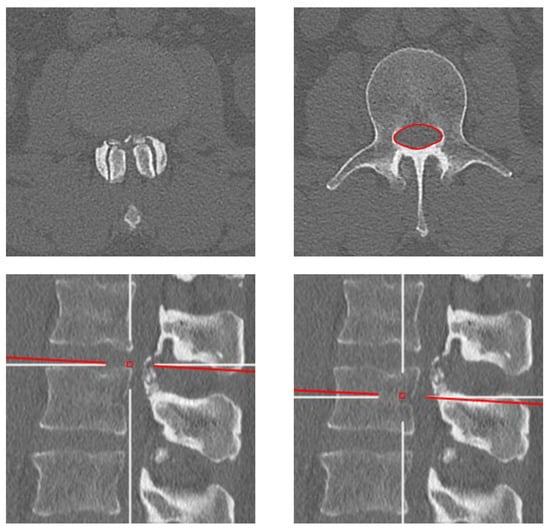

2.3. Image Analysis

Figure 1. Representative axial (top row) and sagittal-reformatted (bottom row) computed tomography images of the lumbar spine at the L2 vertebral level from a male patient born in the 1970s. Note the change in lumbar bone cross-sectional area when measured at the vertebral pedicle level (right column) compared to the intervertebral disc level (left column) due to facet joint osteoarthritis and calcification of the ligamentum flavum in the latter.